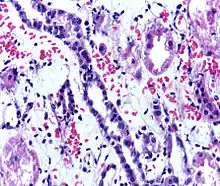

Acute rejection is another possible complication of kidney transplantation; it is graded according to the Banff Classification which incorporates various serologic, molecular and histologic markers to determine the severity of the rejection. Acute rejection can be classified as T-cell mediated, antibody mediated or both (mixed rejection). Common causes of acute rejection include inadequate immunosuppression treatment or non-compliance with the immunosuppressive regiment.[79] Clinical acute rejection (seen in approximately 10-15% of kidney transplants within the first year of transplantation) presents as kidney rejection with associated kidney dysfunction.[79] Subclinical rejection (seen in approximately 5-15% of kidney transplants within the first year of transplantation) presents as rejection incidentally seen on biopsy but with normal kidney function.[79] Acute rejection with onset 3 months or later after transplantation is associated with a worse prognosis.[79] Acute rejection with onset less than 1 year after transplantation is usually T cell mediated, whereas onset greater than 1 year after transplantation is associated with a mixed T cell and antibody mediated inflammation.[79]